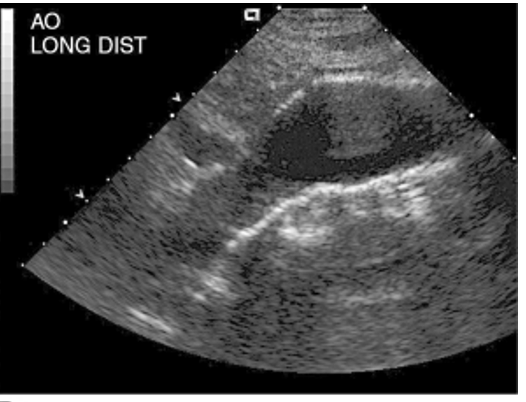

abdominal aortic aneurysm